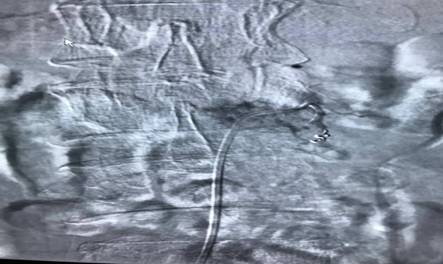

腫瘤血管栓塞前造影圖片

腫瘤血管栓塞后造影圖片